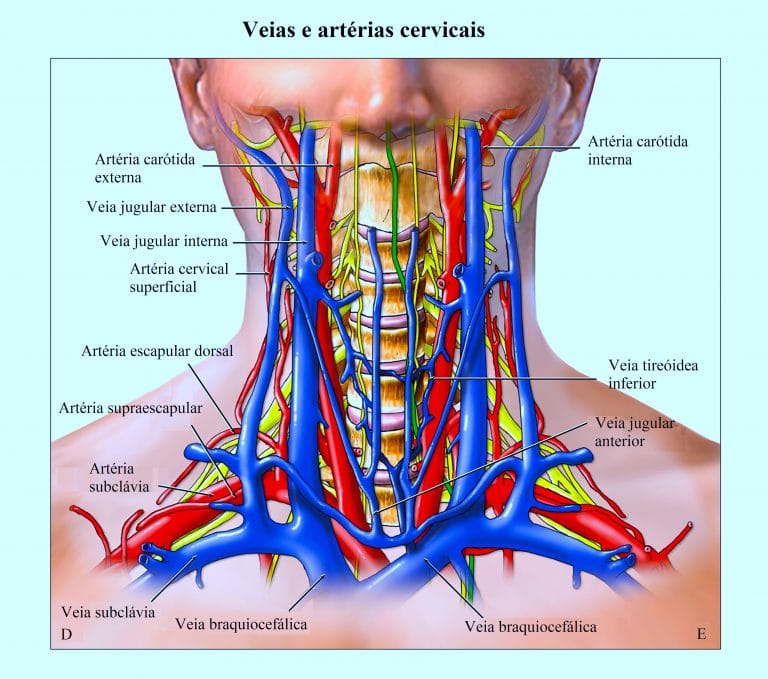

A veia jugular interna situa-se ântero-lateralmente à artéria carótida interna, na sua metade proximal sob o músculo esternocleidomastóideo e sua metade distal no triângulo formado pelas porções clavicular e esternal do músculo esternocleidomastóideo, e pela clavícula. Une-se com a veia subclávia sob o terço proximal da clavícula.

Anatomia dos vasos do pescoço. Fonte – https://www.fisioterapiaparatodos.com/p/causas-do-zumbido-no-ouvido/